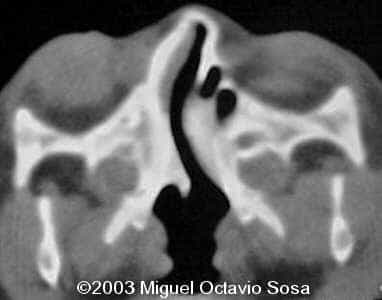

19-year-old primigravida. During third week of pregnancy, she is vaccinated with anti-measles vaccine, without knowing about the pregnancy. There are no important details before the pregnancy. These are images of the face of the fetus. Pay specific attention to the midface.

19-year-old primigravida. During third week of pregnancy, she is vaccinated with anti-measles vaccine, without knowing about the pregnancy. There are no important details before the pregnancy. At 22nd week, an ultrasound is performed demonstrating a single nasal channel on the left side and absence of right nostril.

A female newborn was delivered at 38 week, by cesarean section due to breech presentation. Size of right eye is bigger than left, and there is total absence of the right nostril. Apgar 9 at birth. No complications during postpartum. Newborn is actually under study by plastic surgeon.

These are the 3D CT reconstruction.